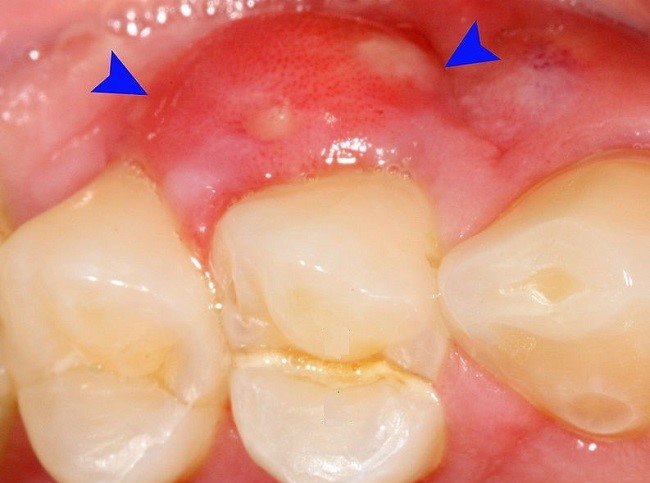

Abses gingiva yaitu abses yang muncul pada gusi. Terjadi saat kantong nanah terbentuk di akar gigi. Diantara jenis-jenis penyakit gigi penderita yang mengalami abses gusi gusinya dapat bernanah.

Orang dewasa memiliki 32 gigi permanen dengan empat jenis gigi serta fungsinya masing-masing. Nanah dapat muncul apabila terjadi inflamasi pada gusi ketika bagian gusi terinfeksi. Bisa terjadi infeksi yang memicu abses gigi.

Abses periodontal yang terbentuk di jaringan gusi. Nanah yang keluar tampak seperti cairan kental yang berwarna kuning putih agak kuning atau bisa juga kuning agak cokelat. Abses ini dimulai di pulpa gigi hingga bagian akar.